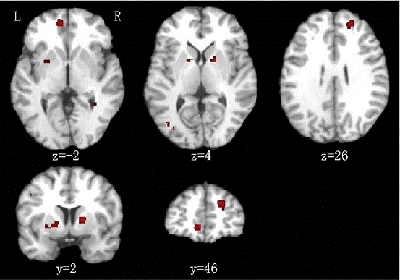

中科院心理所神经心理与应用认知科学实验室陈楚侨研究员和他的团队最近采用了一种严格的方法——激活可能性估计(activation likelihood estimation),来定量地计算精神分裂症白质出现异常的特定脑区。结果表明,精神分裂症病人和控制组相比在额叶和内囊区域的表现出一致的白质容量降低。这些结果支持了精神分裂症白质变化的宏回路理论(macrocircuit theory),而且和陈博士以前发表在Schizophrenia Bulletin上的研究相呼应。如,不同的灰质网络在精神分裂症病人中出现缺损。由于白质是神经连接的基础解剖结构,所以精神分裂症病人的白质异常是合理的。

精神分裂症病人和健康控制组相比表现出白质容量下降,表现在三维图像上为左半球前部分缺少(p<0.01)